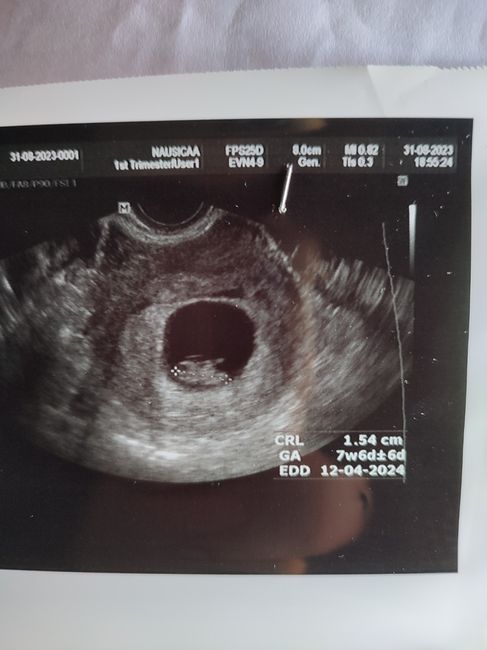

949 giorni fa

Ciao ragazze, so che dovrò aspettare l'ecografia per essere sicura. Ma volevo un vostro parere per pura curiosità 😁 Eco interna 7+6